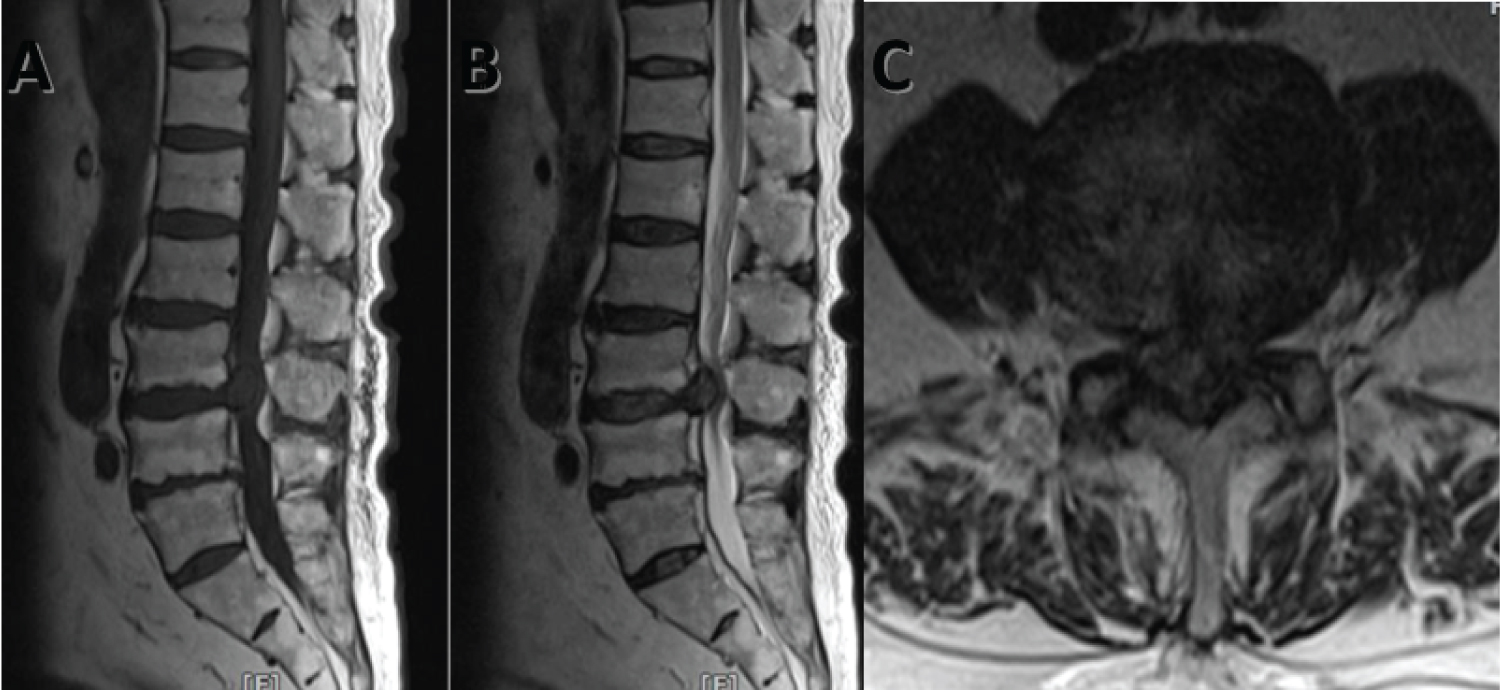

MRI of lumbosacral spine (Figure 1) showed circumferential disc protrusion at L1/L2, L2/L3, L3/L4 and L4/L5 level, the most prominent being L3/L4 disc extrusion causing spinal canal stenosis. No bony lytic lesion seen. Disc height is preserved and there is no significant reduction in signal intensity of the disc. A diagnosis of prolapsed intervertebral disc was made with little suspicion of soft tissue tumor.

Figure 1: A) Sagittal T1 weighted image; B) Sagittal T2 weighted image revealed extrusion of disc from L3/L4 intervertebral disc causing spinal canal stenosis; C) Axial T2 weighted image at disc level. View Figure 1